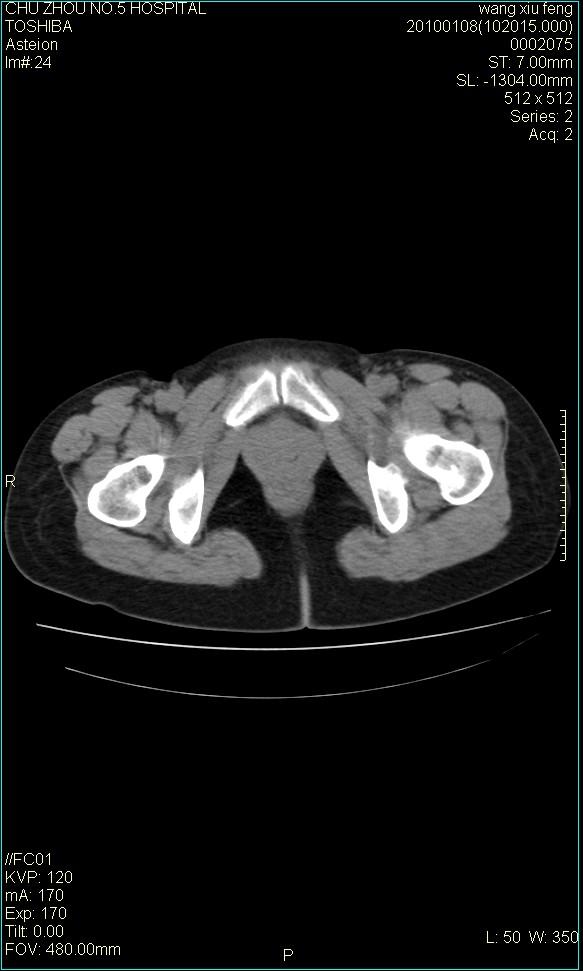

f-41,左乳腺ca术后4年,b超示:子宫右上方囊性包块约5.5*3.4cm,前日行胸部ct平扫未见明显异常。